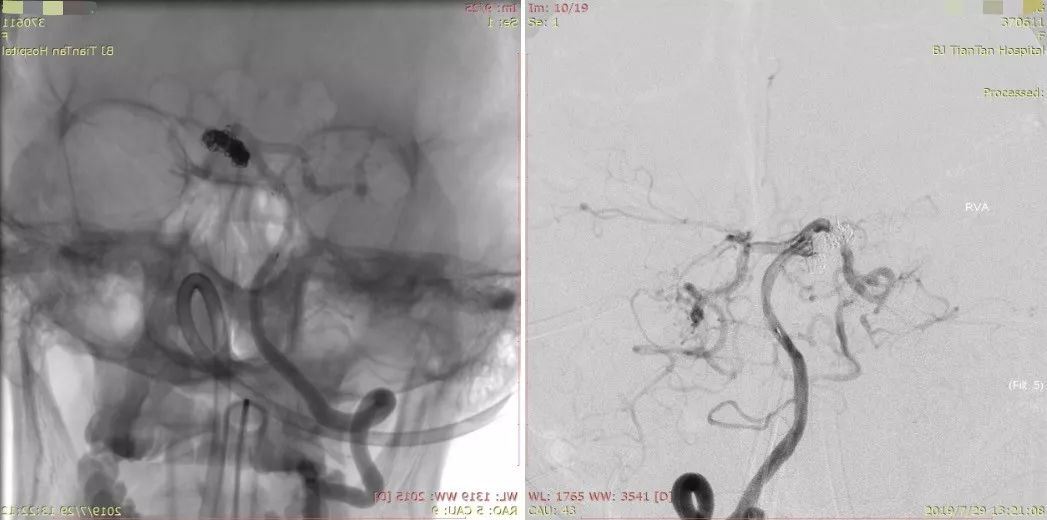

继续填塞弹簧圈,直至达到满意填塞为止(图7)。

图7

术后造影动脉瘤填塞满意,载瘤动脉通畅,同侧大脑后动脉狭窄处未受影响(图8)。

图8